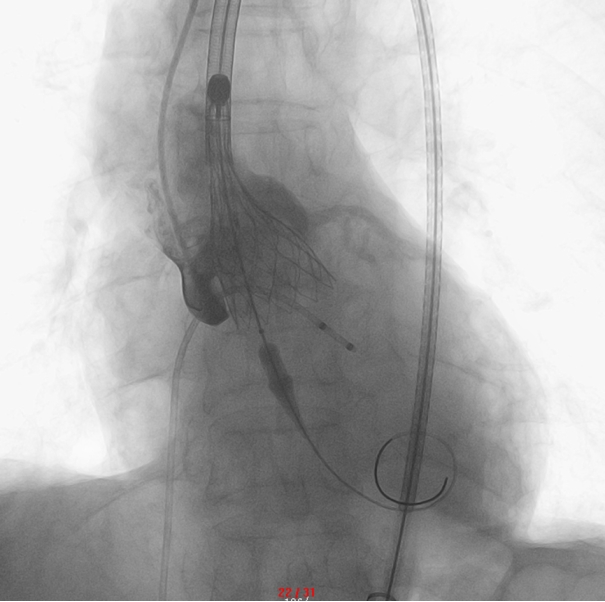

▲ 瓣膜定位释放:精确定位,造影示位置、形态良好